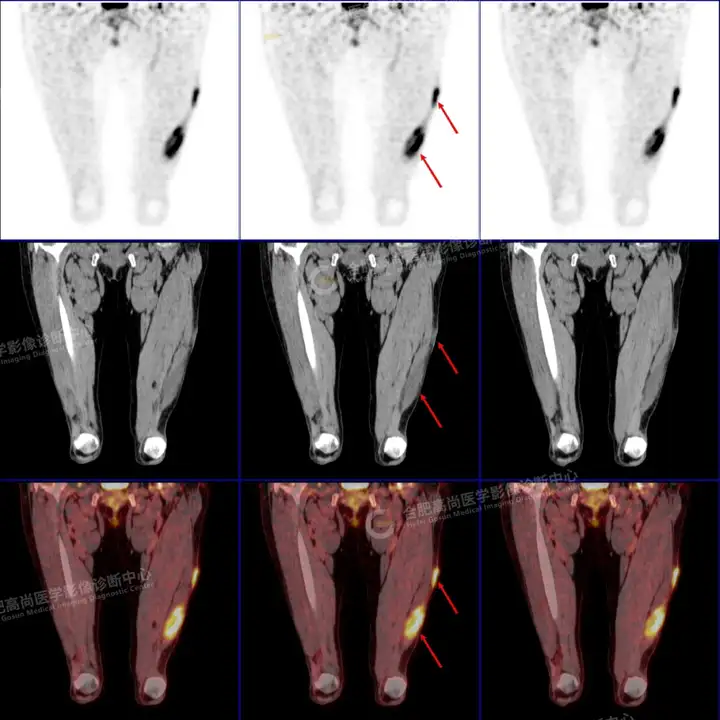

PETCT检查所示:图1、3-17全身多处(双上臂、胸背部、左侧乳腺、左侧腰部、腹壁、双侧臀部及双侧大腿)皮肤下结节及肿块样软组织密度灶,FDG代谢不同程度增高,双侧颈部、左侧锁骨区、纵隔内(1区)及双侧腋窝多发肿大淋巴结,FDG代谢明显增高,符合皮肤来源淋巴瘤。